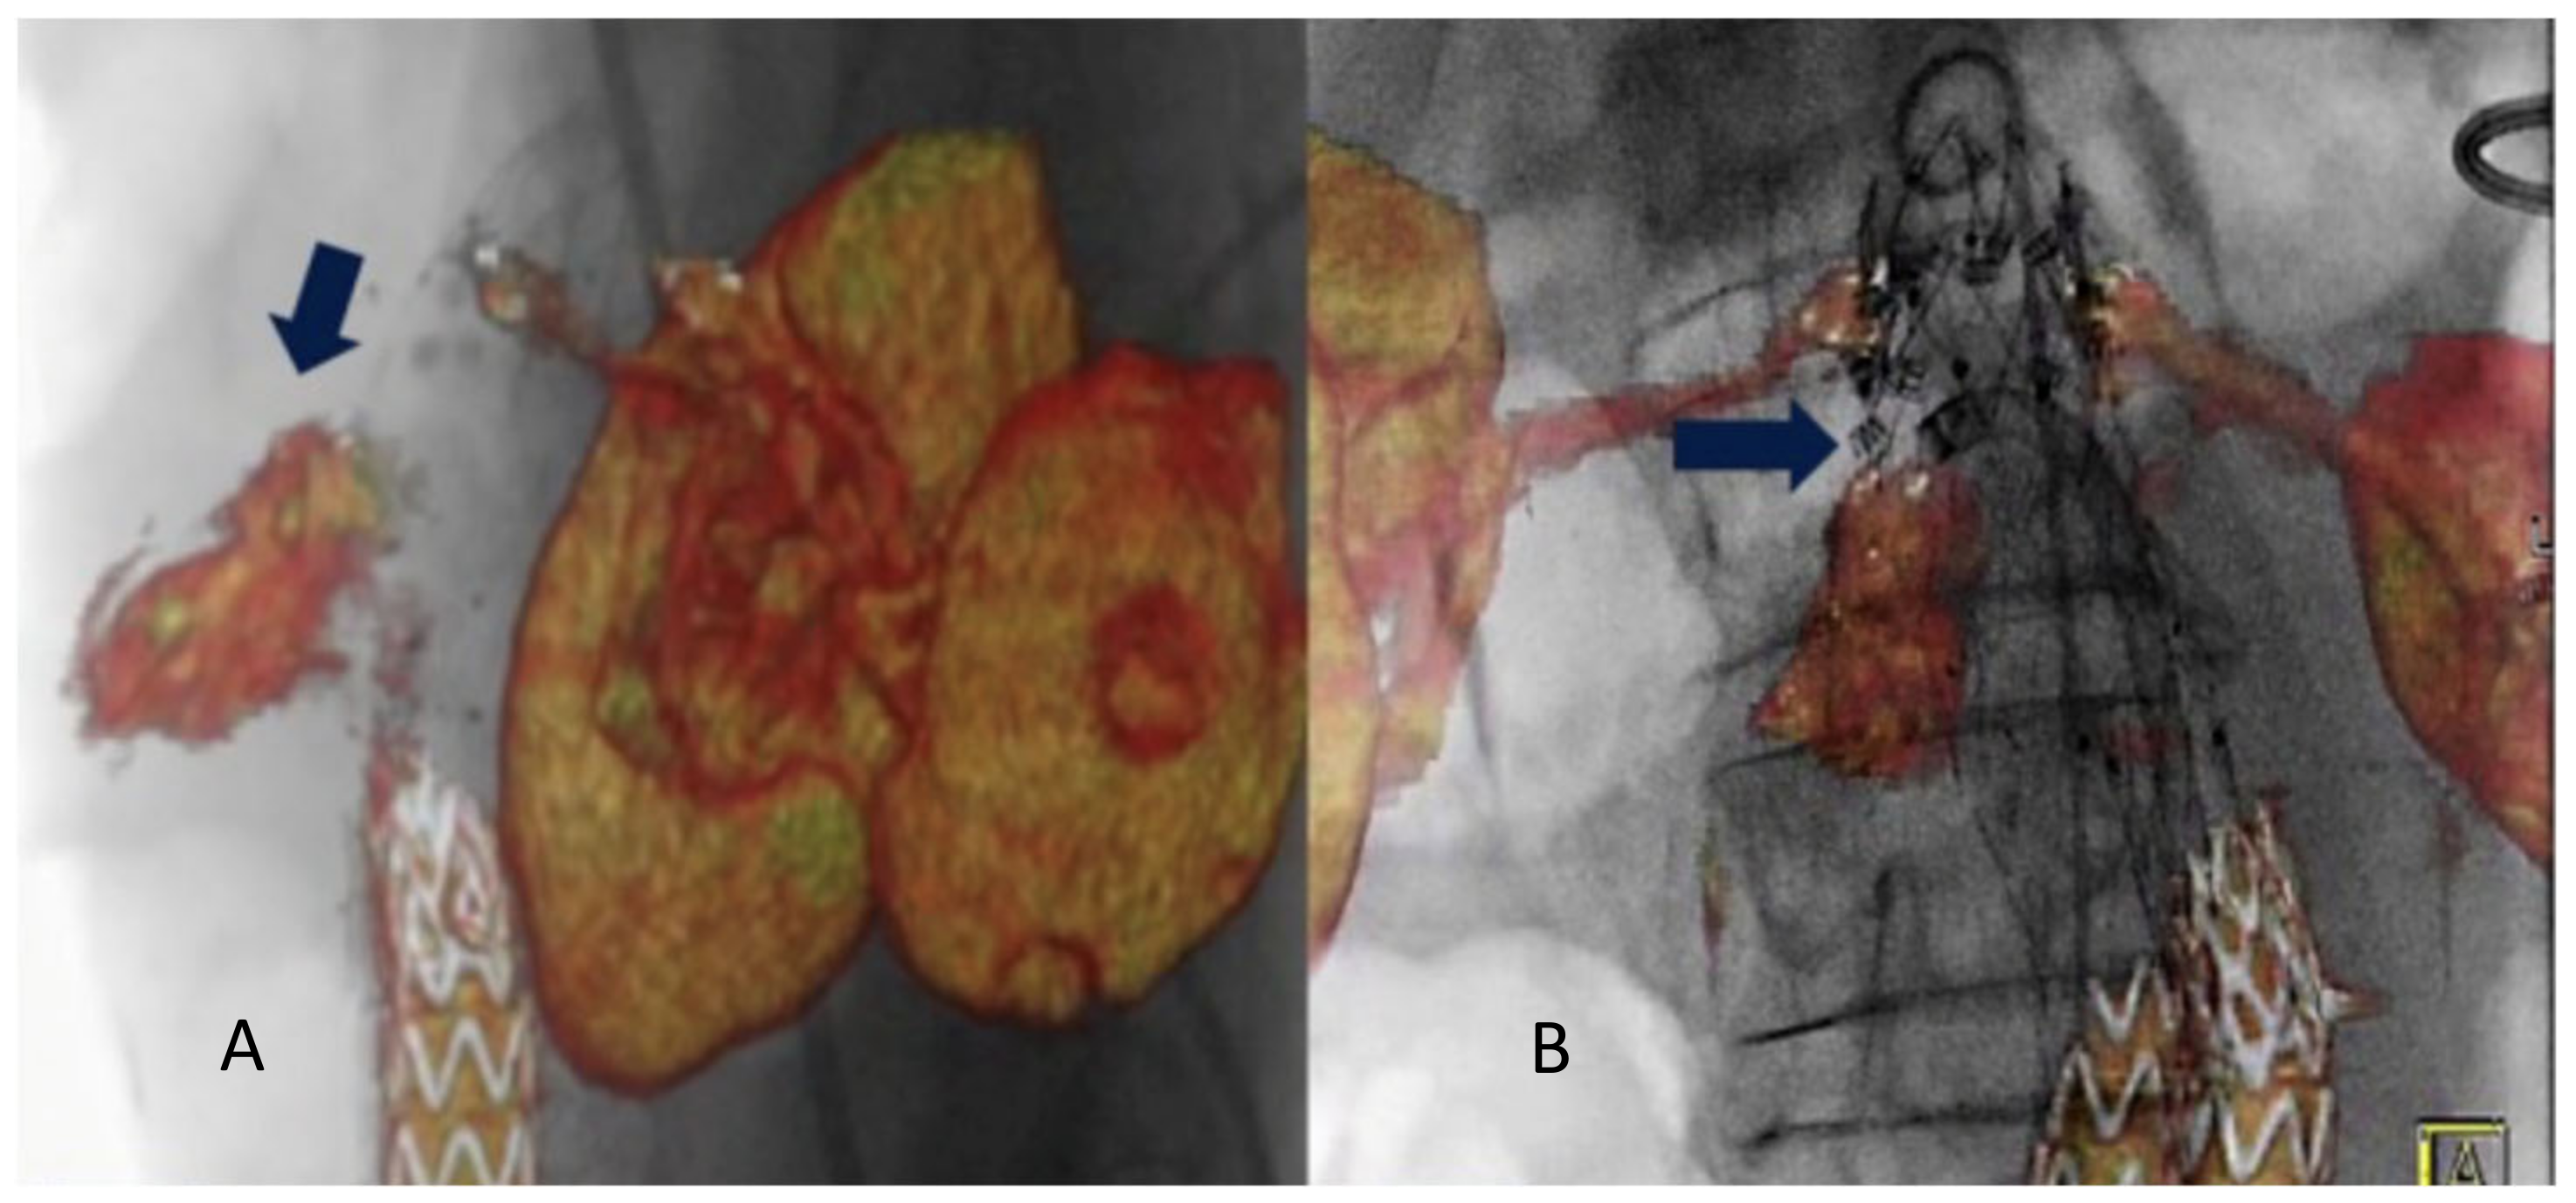

2. Materials and Methods

3. Results

4. Discussion

- Tinelli, G.; De Nigris, F.; Flore, R.; Santoliquido, A.; Tshomba, Y. Endoanchors under 3D image fusion for a type IA endoleak after EVAR. Clin. Case Rep. 2019, 7, 529–532. [Google Scholar] [CrossRef]